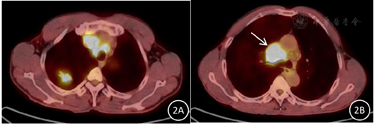

胸部CT、PET-CT、气管镜检查及病理结果(图1,图2,图3,图4,图5,图6)。

患者中年男性,慢性病程,主要表现为咳嗽、咳痰、咯血,查体右锁骨上可触及多个肿大淋巴结,质硬,固定,长期大量吸烟史,proGRP、NSE、CEA明显升高,胸部CT示右肺上叶不规则团块影,边缘分叶,多发毛刺,纵隔及右侧肺门可见多发肿大淋巴结。根据左肺下叶背段支气管黏膜活检为鳞状细胞癌,右肺上叶肺活检为肺腺癌,颈部淋巴结活检为小细胞肺癌。故本例患者肺癌诊断明确,为同时性多原发肺癌。鳞癌是在气管镜下发现,为早期阶段。腺癌的体积比较大,小细胞肺癌原发灶考虑为右侧肺门附近,如图1C、图1D、图2B中白色箭头所示,锁骨上淋巴结穿刺病理证实为小细胞肺癌转移,故在肿瘤标志物上proGRP、CEA明显升高,SCC正常,也符合其临床情况,最终分期:cT2N3M1c,Ⅳb期。